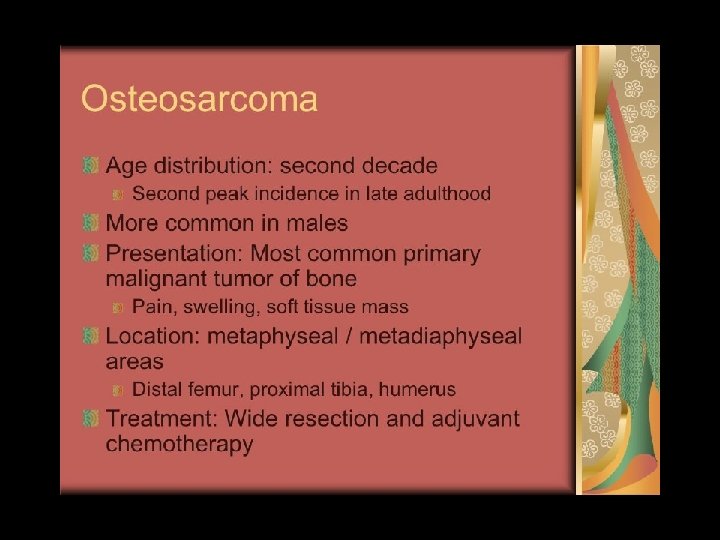

A 14 year old boy presents with pain and a mass above the knee. Take a look at the AP and lateral radiographs first.

In case of Bone Tumors: look for Location! Age Age Behavior

Location and age of patient most important • parameters in classifying a primary bone tumor. Simple to determine from plain • radiographs.